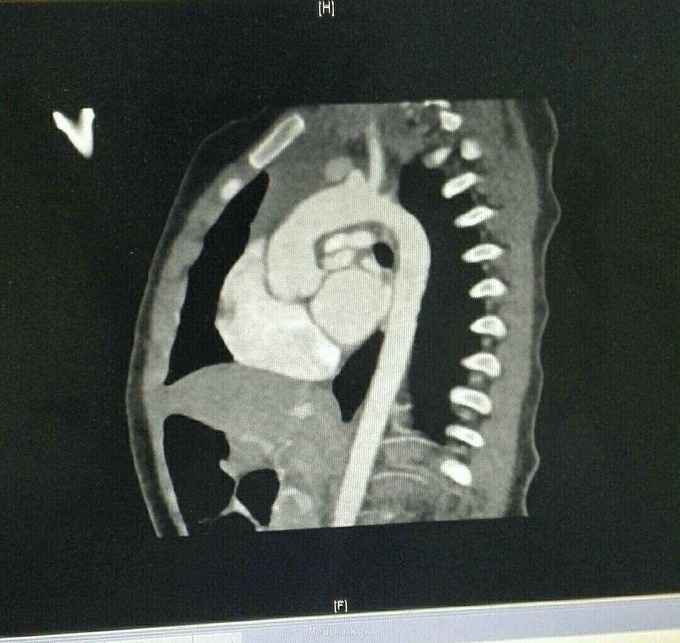

查体 生命体征平稳,口唇发绀,双肺呼吸音清,未闻及干湿性罗音,心律规整,于胸骨左缘可闻及杂音,腹部平软无压痛反跳痛,双下肢无水肿。 辅助检查结果 心脏彩超示 先天性心脏病 法乐氏四联症 肺动脉发育不良 左肺动脉 0.65mm,右肺动脉 0.49mm。 心脏CT检查结果示 先天性心脏病 法乐氏四联症 肺动脉发育不良

先天性心脏病 法乐氏四联症 治疗 患者入院后完善各项术前检查及准备,排除手术禁忌症后为患儿行跟手术治疗。 手术过程 全麻成功后,常规消毒,胸骨正中切口,常规建立体外循环,降温阻断升主动脉后,心脏停跳,切开右房,经卵圆孔放置左心引流,经右心室流出道切口,切除肥厚的隔束及壁束,切开肺动脉瓣交界处粘连,可通过9号探子,左右肺动脉可通过7号探子,取涤纶补片修补室间隔缺损,已带瓣牛心包补片加宽右室流出道,开放循环,心脏复跳,手术过程顺利,患者安反监护室。